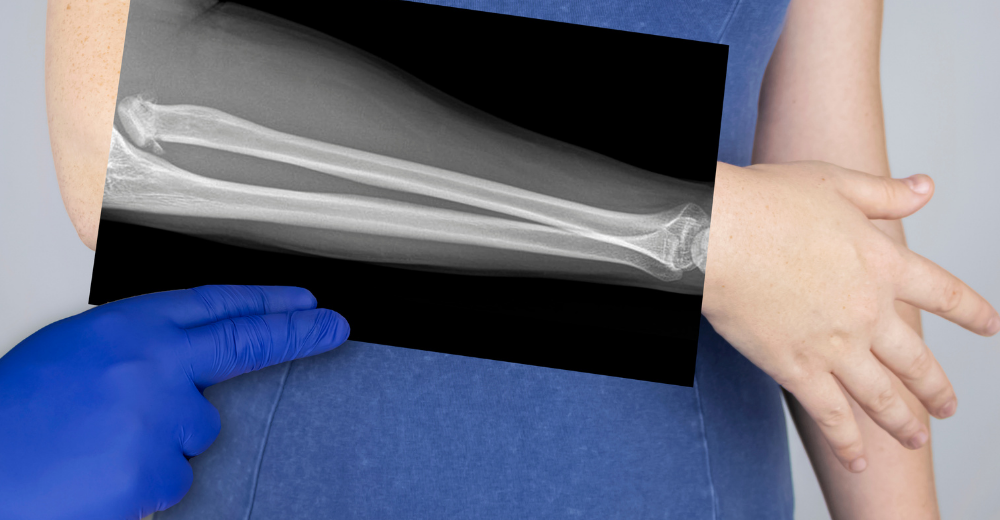

L’Esame RX Avambraccio viene eseguito da un tecnico radiologo specializzato presso il Poliambulatorio S-Medical Group di Sora. Il paziente viene posizionato correttamente per permettere l’acquisizione delle immagini da diverse angolazioni:

1. Preparazione: Il paziente viene invitato a rimuovere eventuali oggetti metallici che potrebbero interferire con le immagini.

2. Posizionamento: L’avambraccio viene posizionato su un supporto rigido e le proiezioni vengono scelte in base all’area di interesse.

3. Emissione dei Raggi X: Una macchina emette raggi X che attraversano l’avambraccio, proiettando le immagini su un monitor.

4. Analisi delle Immagini: Le immagini ottenute vengono analizzate per identificare eventuali anomalie o patologie.

Il tempo complessivo dell’esame è breve e, in generale, non supera i 15 minuti.